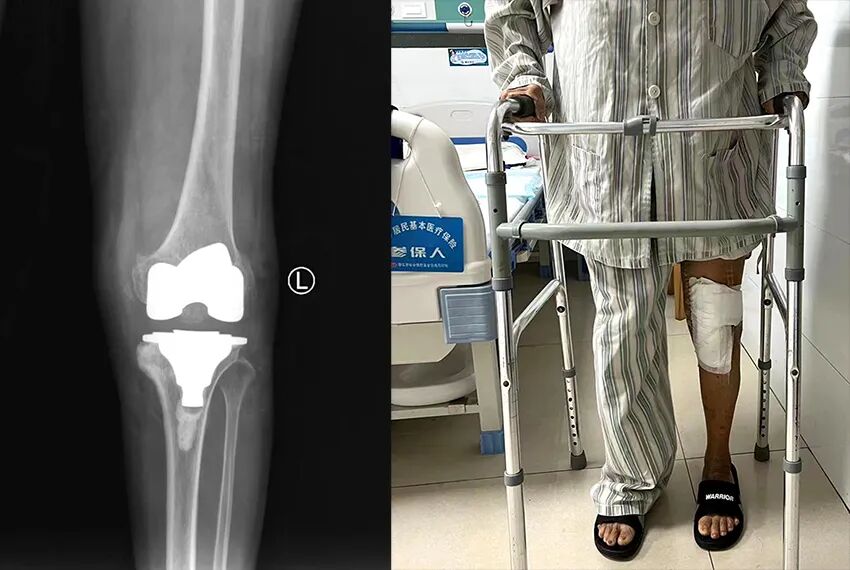

在家人的陪同下,慕名找到湛江骨科醫院首席專家雷文黎教授就診。入院后經過全面的體格檢查、化驗、x線及CT檢查,發現左膝脛骨內髁大量缺損,脛骨、股骨及髕骨關節面周圍有大量骨贅增生,關節嚴重內翻屈曲畸形,內側副韌帶緊張,外側副韌帶松弛,關節活動受限,雷文黎教授及其團隊多次反復研究病情,應用現代最先進的3D打印技術,根據其病情制訂了三套手術方案,并對每套方案制定周密、詳細的實施計劃,第一套方案是最經濟、長期效果最好的關節表面置換術,也是難度最大,要求最精細而且最考驗醫生經驗的方案,其他兩個方案是第一個方案的替代與補充,但用的耗材比較昂貴,病人經濟負擔高。在麻醉科的全力配合下,雷文黎教授通過精準的截骨,切除關節內側、后側骨贅,并縮小脛骨平臺內側,使得內側副韌帶張力減小,內外側軟組織平衡,為實施第一個方案創造了條件,順利地為龐奶奶進行了膝關節表面置換手術,術后患者關節疼痛及畸形完全矯正,屈曲、伸直功能完全恢復。

康復出院的龐奶奶不用人攙扶,高興地在病房里走了兩圈,她邊走邊激動地說:“飽受10多年的膝關節疼痛折磨,現在走路再也感覺不到,又可以正常行走,真的太感謝雷教授了!”一旁的家屬看到老人家康復這么好甚是欣慰。